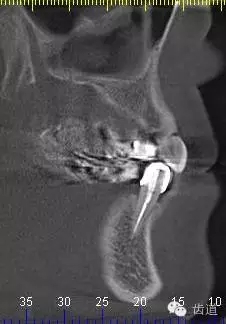

9、34CBCT

10、 26,27CBCT